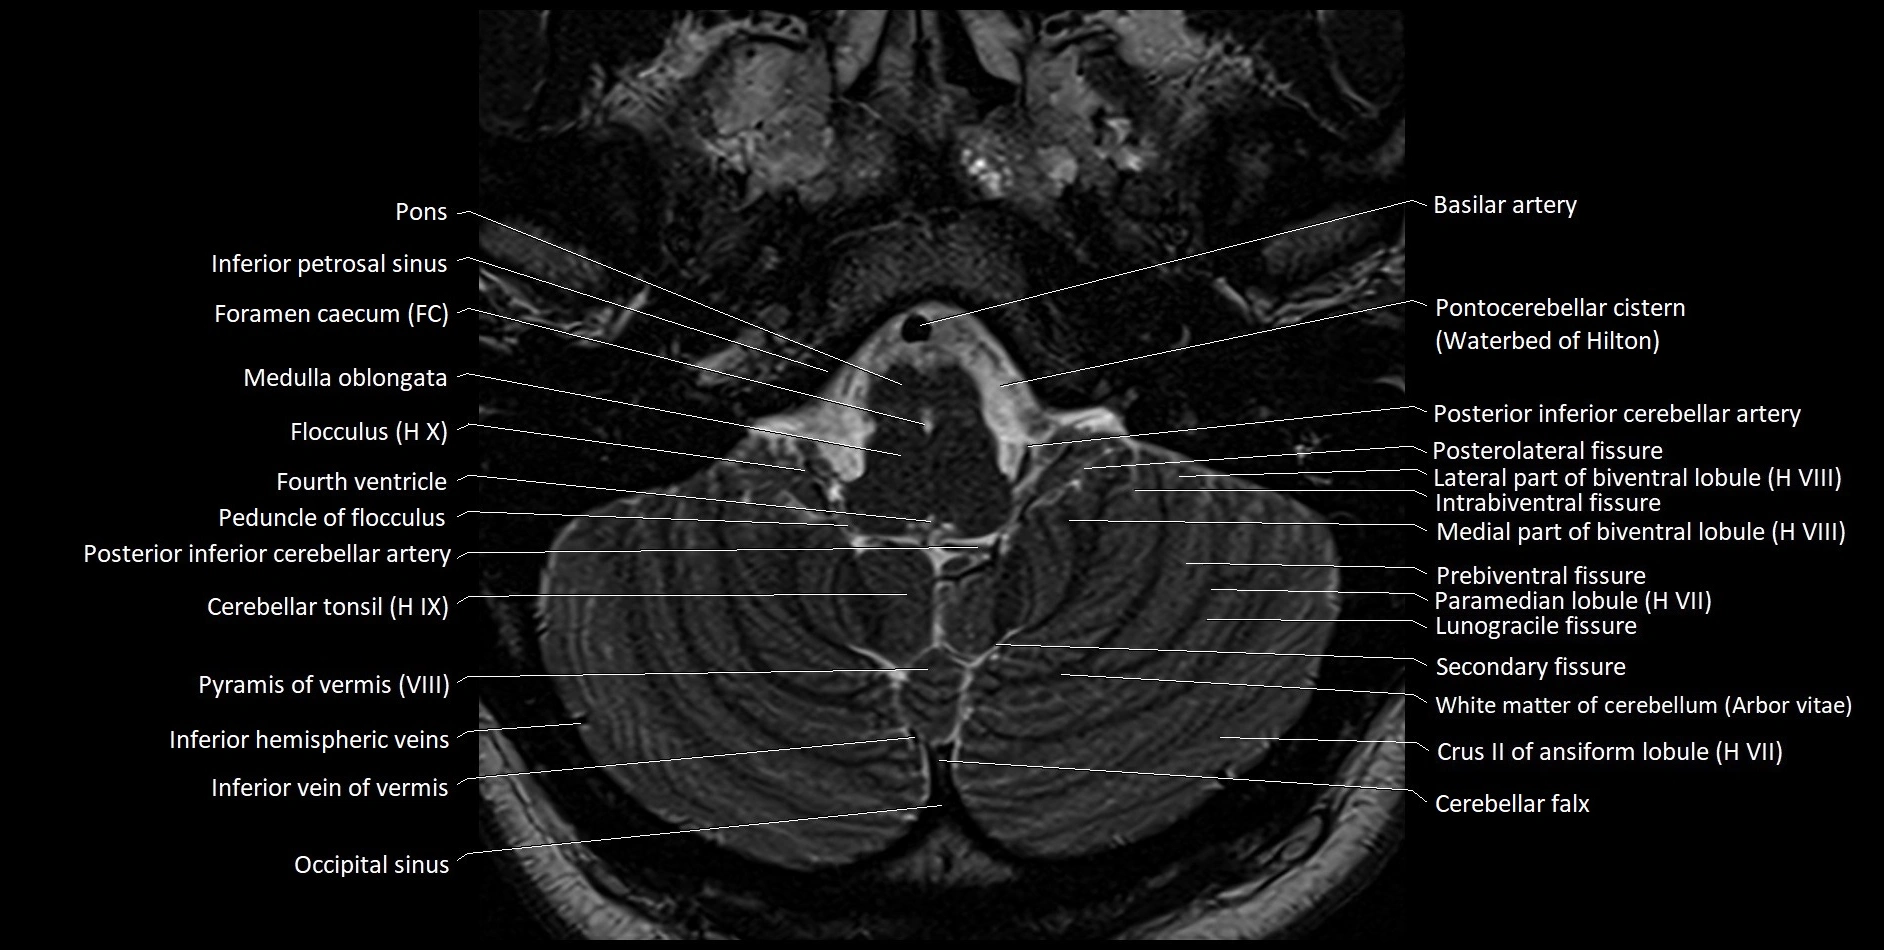

- Biventral lobule (HVIII) of cerebellum

- Cerebellar tonsil (H IX)

- Crus II of ansiform lobule of cerebellum

- Flocculus

- Inferior petrosal sinus

- Inferior vein of vermis

- Intrabiventral Fissure of Biventral Lobule

- Lateral part of biventeral lobule

- Medial part of biventeral lobule

- Occipital sinus

- Paramedian lobule (HVII) of cerebellum

- Peduncle of flocculus

- Posterior inferior cerebellar artery

- Posterolateral fissure

- Prebiventral fissure

- Pyramid of vermis (VIII)

- Secondary fissure